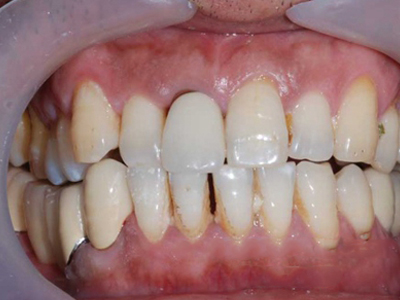

牙龈退缩上排多颗牙的牙根暴露图

牙龈退缩导致上排多颗牙齿的牙龈回缩,部分牙根暴露在外,伴有牙齿松动、口臭等症状,是由于牙周炎、局部受力过大等因素导致。